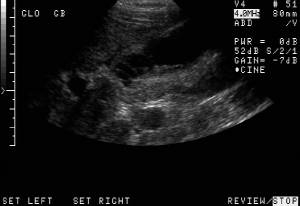

RADIOLOGY: GASTROINTESTINAL: GI: Case# 34606: ADENOMYOMATOSIS. 28 year old woman with intermittent right upper quadrant pain for approximately one year.